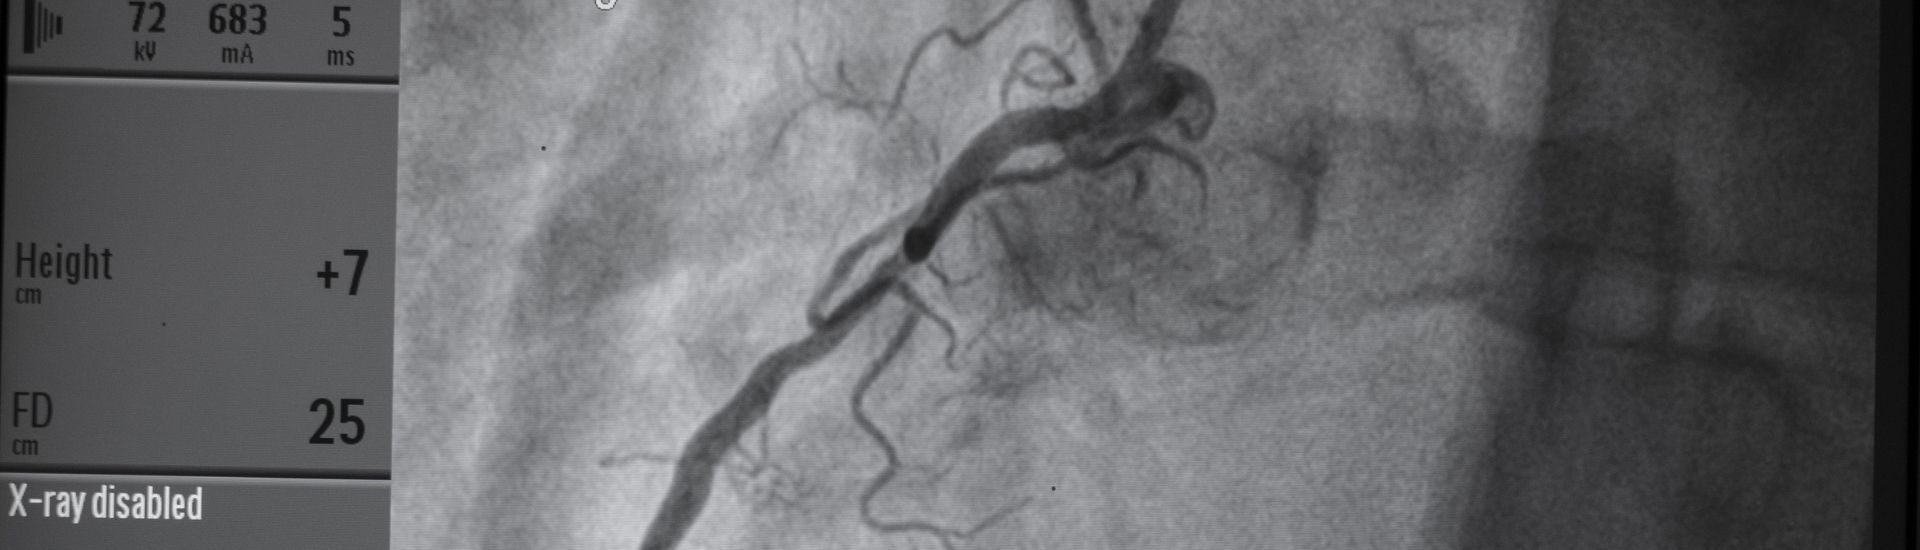

تصوير الشرايين التاجية (القسطرة التشخيصية) في تركيا

يُعد تصوير الشرايين التاجية — المعروف أيضًا باسم القسطرة التشخيصية للقلب — إجراءً طفيف التوغل يستخدم لتصوير الشرايين التاجية وتحديد وجود انسداد أو تضيق أو أي خلل يؤثر على تدفق الدم إلى عضلة القلب.

يُعتبر هذا الفحص المعيار الذهبي لتقييم آلام الصدر، وضيق التنفس، ونتائج اختبار الجهد غير الطبيعية، أو الاشتباه بمرض الشرايين التاجية.

• التصوير الفوري

تُستخدم الأشعة السينية الرقمية لرؤية تدفق الدم واكتشاف الانسدادات.

• التشخيص

يقوم طبيب القلب بتقييم:

• حجم الشرايين

• درجة التضيق

• طبيعة الترسبات

• الحاجة إلى تركيب دعامة أو تعديل العلاج الدوائي